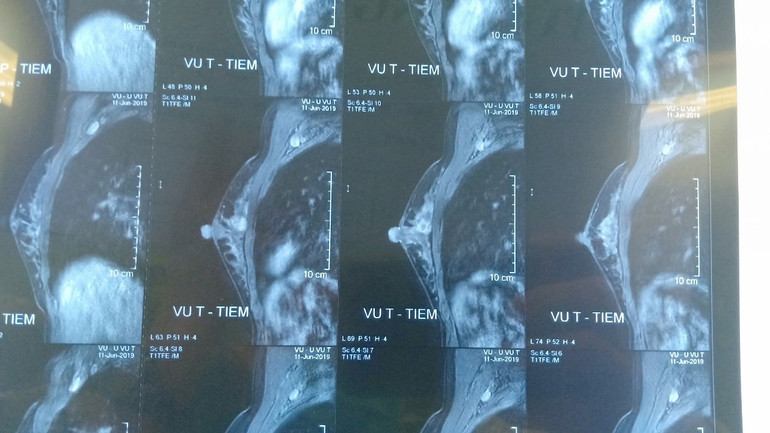

Hình ảnh phim chụp khối u của bệnh nhân trước khi phẫu thuật.